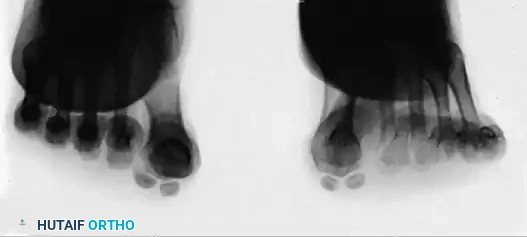

Techniques for Axial Imaging

Proper positioning is paramount for a diagnostic axial view. The patient can be positioned standing on an inclined plane to simulate weight-bearing forces.

FIGURE 81-103 A: View may be taken with the patient standing on an inclined plane.

FIGURE 81-103 B: Axial sesamoid view taken from the front while the patient stands on an inclined plane.